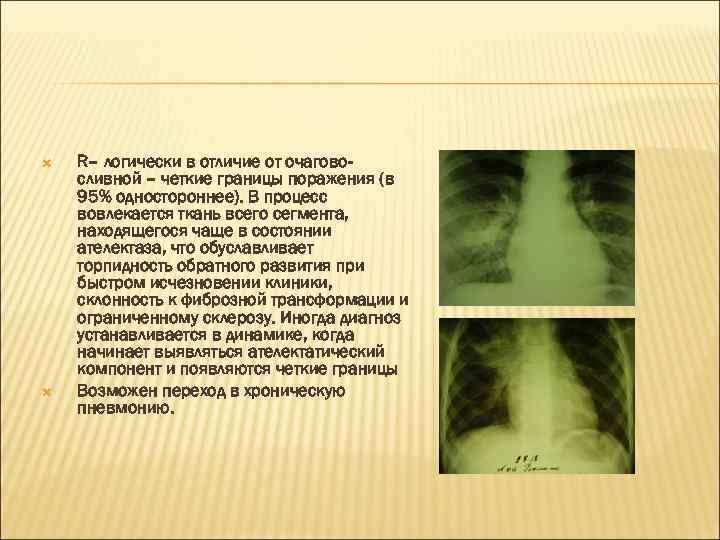

R– логически в отличие от очаговосливной – четкие границы поражения (в 95% одностороннее). В процесс вовлекается ткань всего сегмента, находящегося чаще в состоянии ателектаза, что обуславливает торпидность обратного развития при быстром исчезновении клиники, склонность к фиброзной трансформации и ограниченному склерозу. Иногда диагноз устанавливается в динамике, когда начинает выявляться ателектатический компонент и появляются четкие границы Возможен переход в хроническую пневмонию.